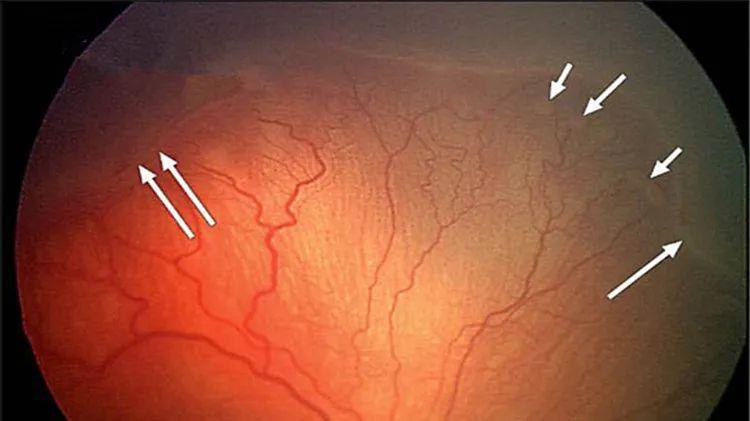

急性白血病的眼部直接浸润病变较为少见,更多见的是出血、血栓形成、贫血等带来的继发眼底改变。视网膜出血、棉绒斑是急性白血病累及眼底时的常见表现,也可出现眼底 Roth 斑。如图可见急性白血病眼底火焰状出血、棉绒斑和 Roth 斑同时存在。